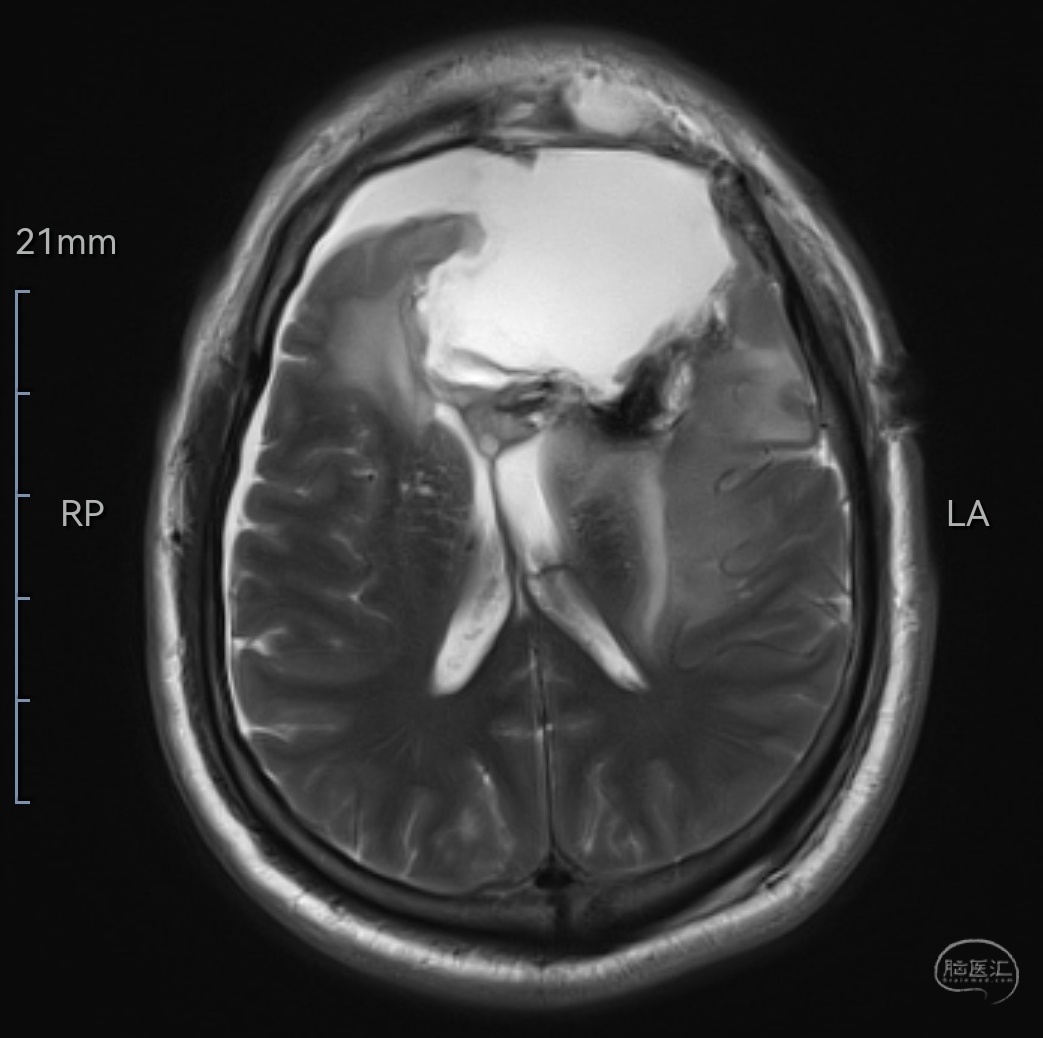

MRIT2相轴位示肿瘤等高信号,位于双侧额叶,左侧为主,已侵犯至胼胝体嘴、膝部及左侧颞岛叶,伴有明显水肿